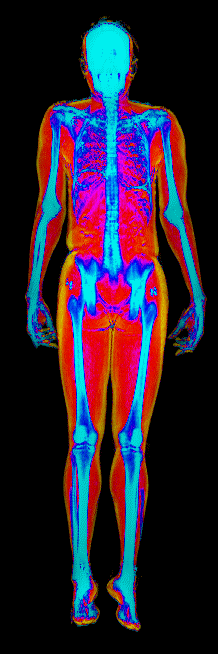

This page features real, anonymized DEXA scan images from BodyStats clients, organized by gender and body fat percentage in 5% increments. DEXA (Dual-Energy X-ray Absorptiometry) is the clinical gold standard for measuring body composition — far more accurate than scales, calipers, or visual estimates.

Each colorized scan shows the distribution of fat tissue (shown in warmer colors) and lean tissue (cooler colors) throughout the body. Compare your own DEXA scan to others in your range, or see what different body fat levels actually look like on a scan.

Male DEXA Scans by Body Fat %

10 to 15% body fat